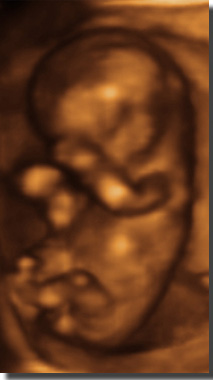

Live 3/4 D Ultraschall

12. SSW

30.

SSW

35. SSW

Baby

vor der Geburt im 3D Ultraschall und gleiches Baby nach der Geburt!